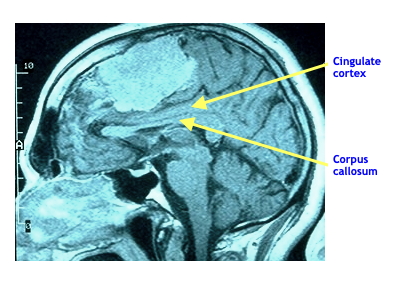

- Magnetic Resonance Imaging (MRI): Body tissue is subjected to a strong magnetic field which is turned on and off rapidly in the presence of a radio wave. The atoms of the brain change their alignment (spin) because of the magnetic field when it is on and give off characteristic radio signal when it is turned off. A detector reads those signals and, using a computer, can map the structure of the tissue. Developed in the 1970s and used clinically beginning in the 1980s.

In the MRI image on the right, the patient appears to have a large tumor growing in the mid-portion of the brain. This has compressed the cingulate cortex and is pressing down on the corpus callosum.